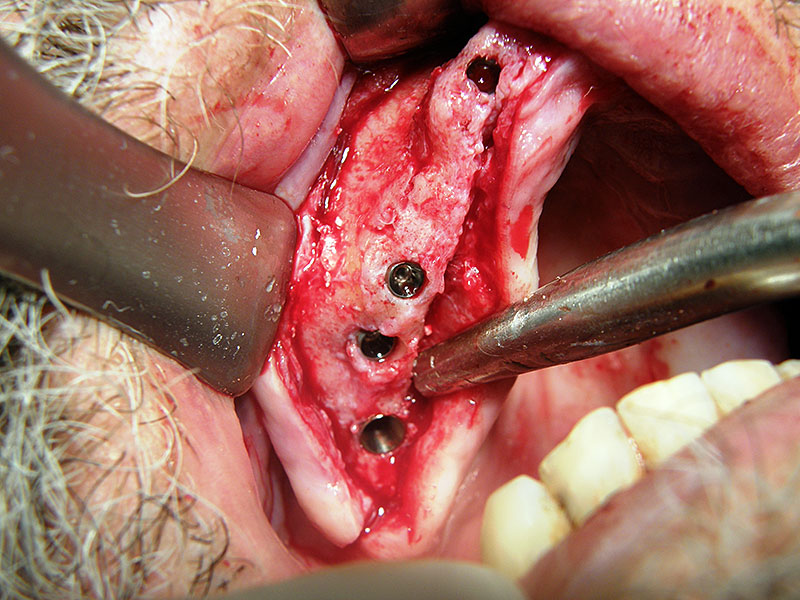

Oralna kirurgija